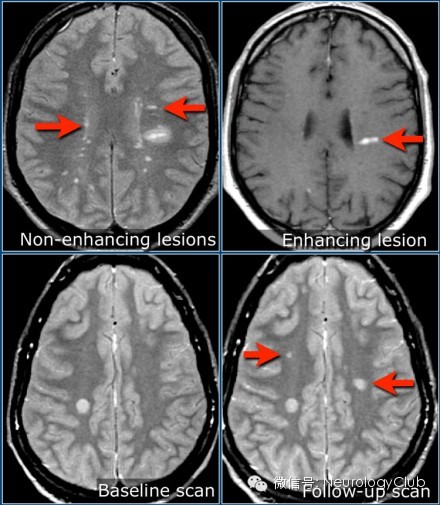

第五方面:大小分布与强化

1、大多直径小于5mm,皮质多见

2、不均匀强化、均匀强化、环形强化、开环强化(特征之一)

3、强化与变化:部分病灶很快消失,新的病灶很快出现。